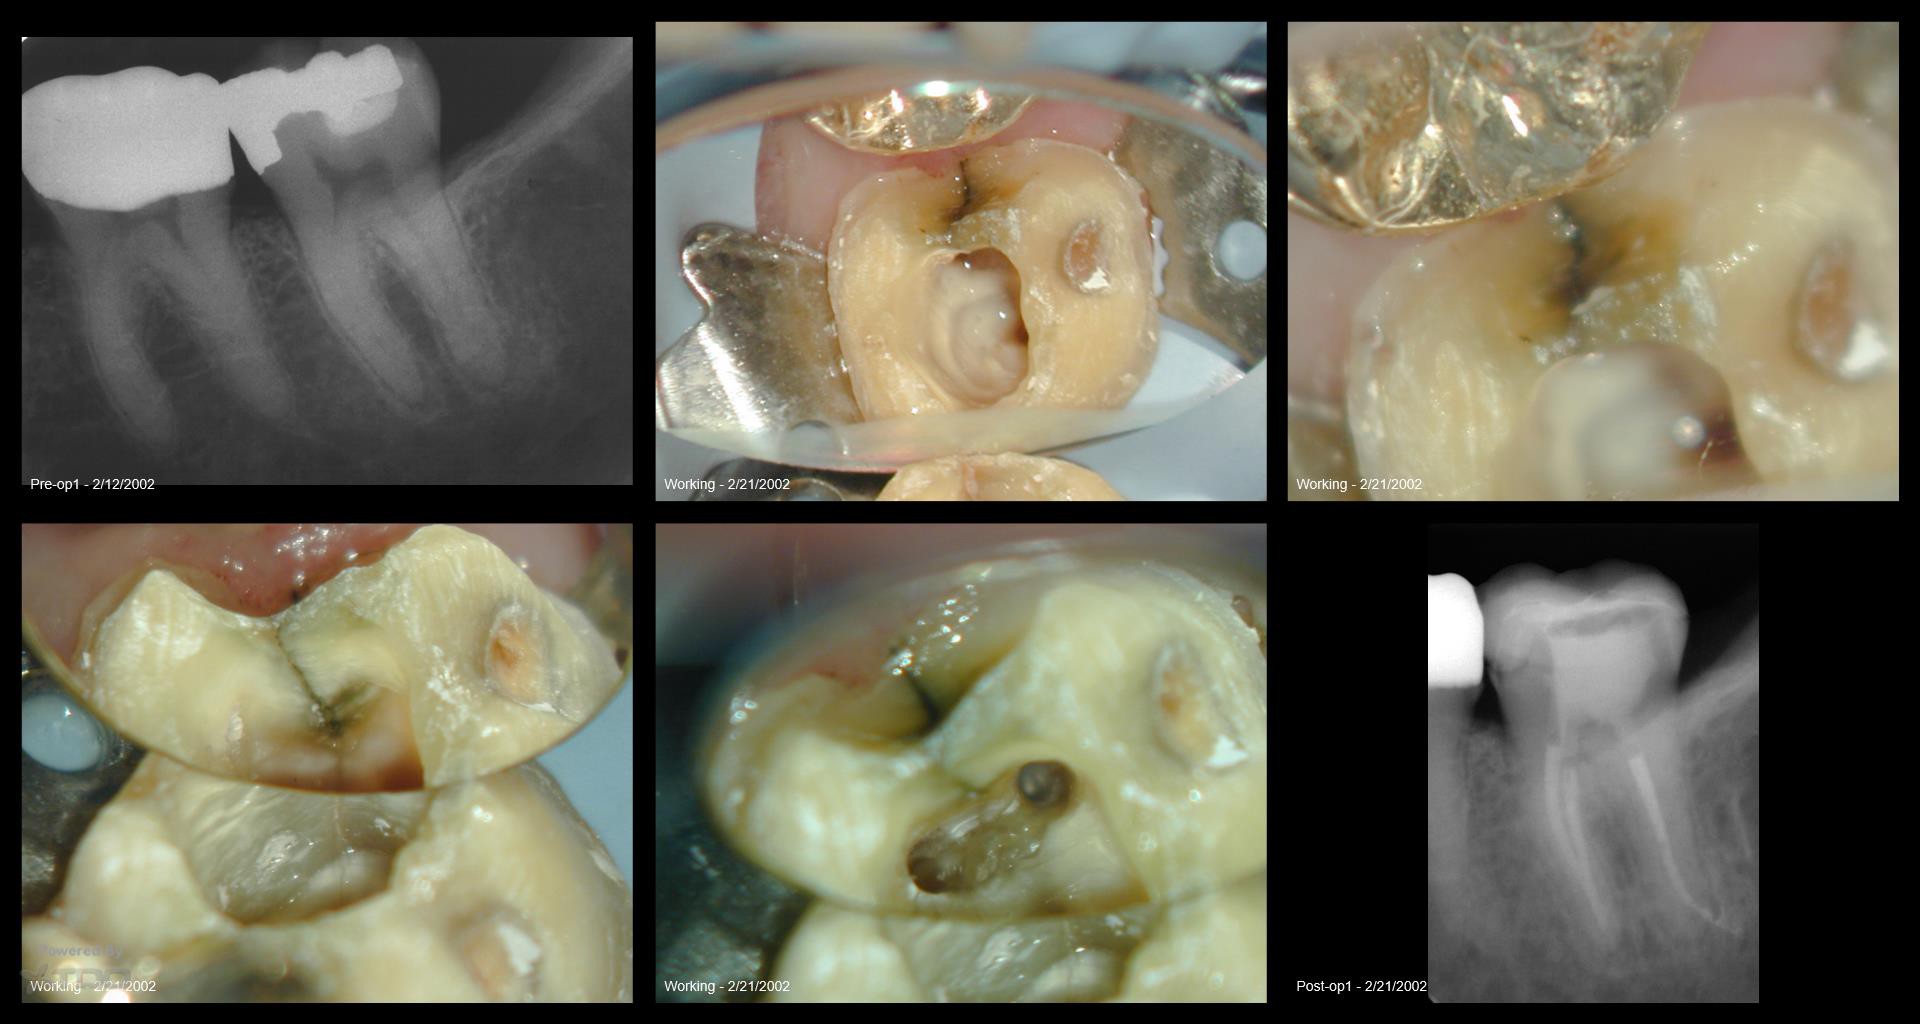

16 yr recall os a fracture

Collage-2140634747-Page00